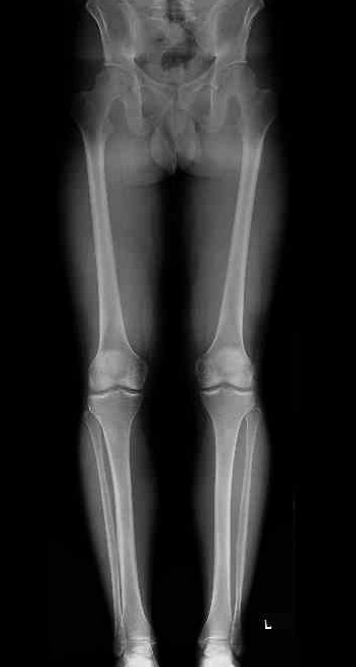

Example of medial OA

- anatomical angle 1o valgus

- correct to 8o valgus

- need to correct 7o

Measure anatomic femoral tibial angle